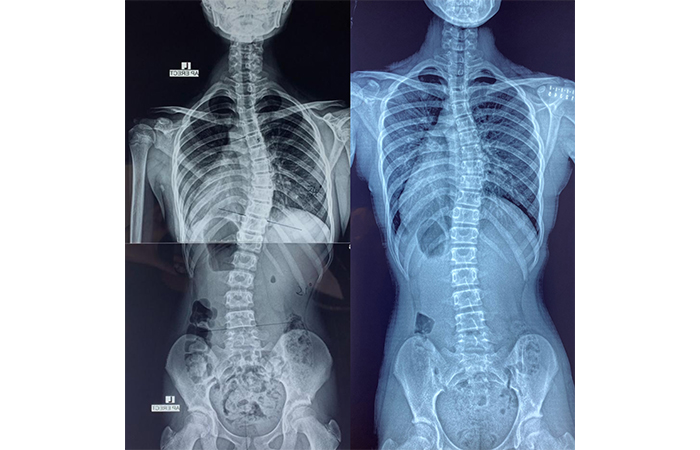

脊柱側彎是指脊骨向左或向右彎曲至呈現「C」形或「S」形,超過十度或以上。大部分脊柱側彎的成因不明,而且通常在青春期十至十五歲出現,女性為多,我們稱之為「青少年原發性脊柱側彎」。脊椎側彎常見的特徵有高、低膊,腰部大細邊,盆骨左右不對稱或長短腳等。 另外亦有成人退化性脊柱側彎。

脊柱側彎多發於青春期,及早發現及適當的治療,有效停止甚至減少彎度惡化,減少需要做手術的嚴重情況。保持弧度不惡化亦能避免中老出現的痛症。我們相信每一位脊柱側彎的患者都可通過專業的運動治療增加肌力、柔韌度及改良姿勢,以改善側彎帶來的不良後果。